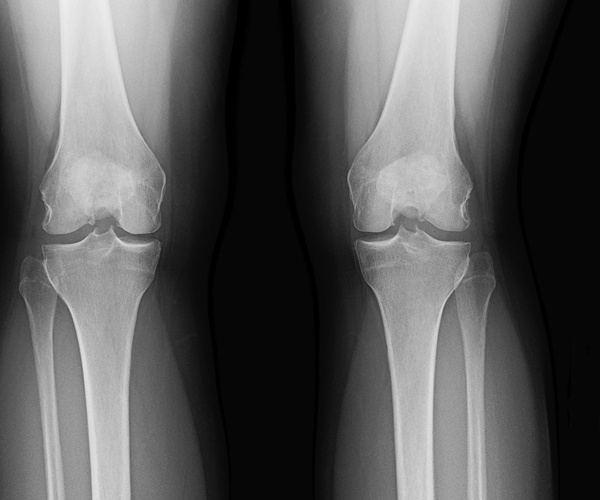

New drug stops arthritis bone loss

A new drug might be able to save a person’s knees from the ravages of osteoarthritis, researchers report.

People taking the drug, code named MIV-711, had less bone and cartilage loss than others given a placebo.

“We know that bone slowly changes shape as knee osteoarthritis progresses,” said lead researcher Philip Conaghan, a professor at the Leeds Institute of Rheumatic and Musculoskeletal Medicine, in the United Kingdom. “This is the first study to show a drug can slow this osteoarthritis bone change, and one dose of the drug also slowed cartilage loss.”

MIV-711 works by inhibiting the action of cathepsin K, an enzyme that promotes breakdown of old bone and cartilage in humans as new bone and cartilage replaces it.

This sort of turnover is natural in the human skeletal system, Katz said, but osteoarthritis — the “wear and tear” form of arthritis — occurs when the balance is disrupted and old bone is removed faster than new bone can replace it.

The participants underwent the therapy for 26 weeks, during which the researchers used MRI scans to watch for changes in bone shape, Conaghan said.

People given MIV-711 appeared to have less bone turnover and removal of old bone than those taking a placebo. They also lost less cartilage and collagen, the main structural protein in the body’s connective tissues, the researchers found.

“This drug stops bone being absorbed and therefore tends to improve bone quality,” Conaghan said. “A big issue will be whether slowing bone shape change will result in reduced symptoms months or years later.”